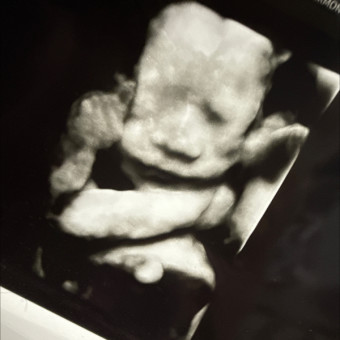

Lincoln's Registry❤️

Abbie Alfred & Harman Harman

December 20, 2025